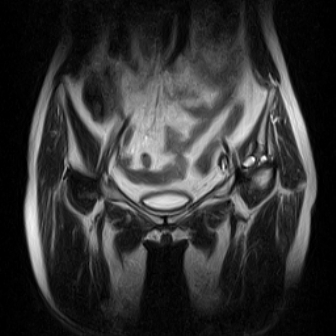

片子不全,应该是左侧股骨头无菌坏死,右侧似乎没问题,到正规医院治疗,千万别看广告去小医院,吃中药什么的,都是骗人的(说了也白说,百分百都得让人骗点钱才甘心。)

应该是左侧股骨头无菌坏死